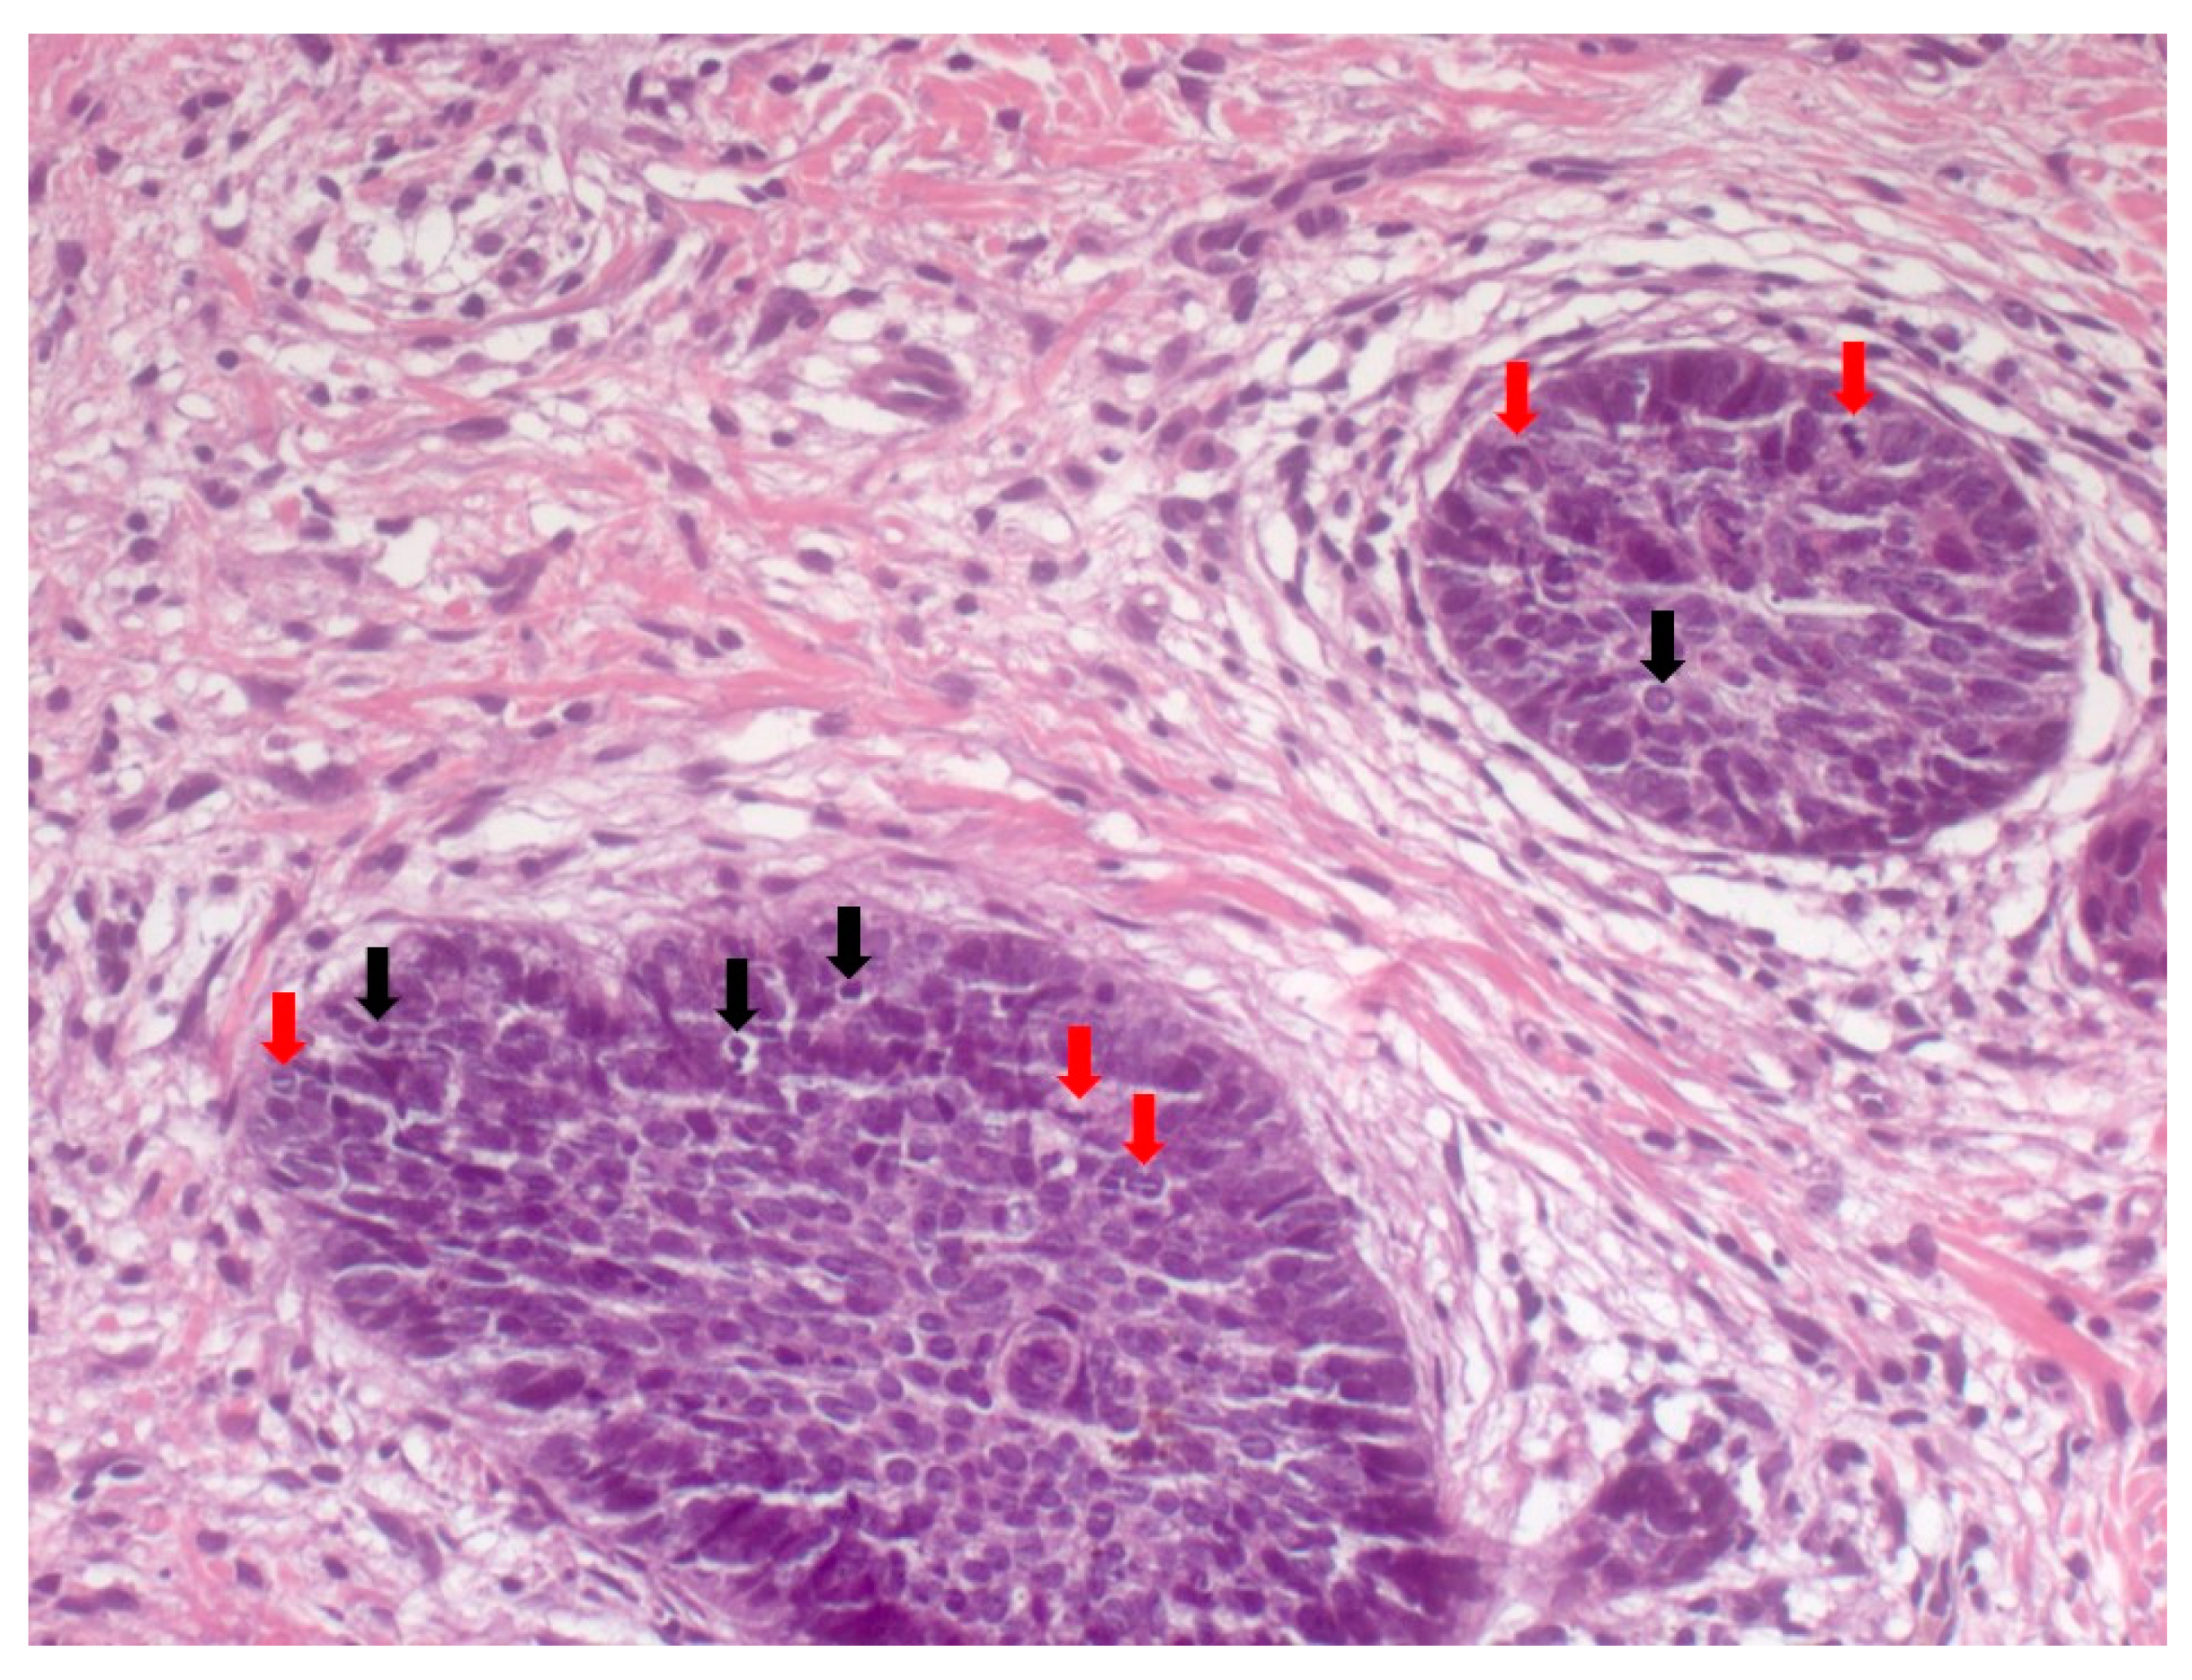

4. Histopathological Features of BCC

- Paolino, G.; Donati, M.; Didona, D.; Mercuri, S.R.; Cantisani, C. Histology of Non-Melanoma Skin Cancers: An Update. Biomedicines 2017, 5, 71. [Google Scholar] [CrossRef] [Green Version]